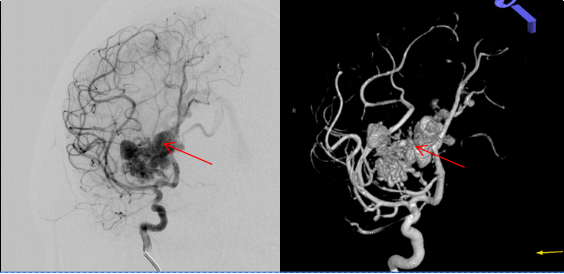

▲经过给患者“量身定制”的介入栓塞术治疗后,畸形血管团完全消失,正常的脑动脉及分支保留通畅

乘胜追击,刻不容缓!征得家属同意后,冯大勤立即带领神经外科脑血管病专业团队,在麻醉科、放射学科介入手术室等团队密切配合下,有条不紊地给叶女士完成了“全脑血管造影术”“球囊辅助下脑动静脉畸形栓塞术”和“支架辅助血管重建术”,在保留病灶周围正常血管结构的前提下成功栓塞了畸形血管团。手术一气呵成,体现了微创、高效、安全和个性化的理念与特点。术后经麻醉复苏,患者意识也恢复如初。